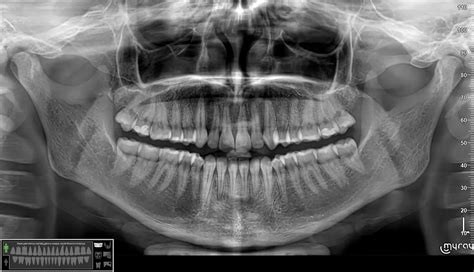

Operacinis mikroskopas - vienas svarbiausių odontologijos priemonių efektyviam dantų, o ypač endodontijos srityje, gydymui. Mikroskopas odontologui padeda atrasti dažniausiai sunkiai aptinkamą ketvirtąjį krūminio danties kanalą arba užkalkėjusius danties kanalus. Nesterilizuoti ir neužpildyti plomba šie kanalai yra būsimas bakterinės infekcijos židinys.

Patyrę klinikos gydytojai siekia ilgaamžių rezultatų. Sėkmingą endodontinį gydymą užtikrina „OksDenta“ klinikoje naudojamas mikroskopas, kuris padeda dantų šaknų kanalų gydymą atlikti ypač tiksliai ir saugiai.

Sėkmingą endodontinį gydymą užtikrina „OksDenta“ klinikoje naudojamas mikroskopas, kuris padeda dantų šaknų kanalų gydymą atlikti ypač tiksliai ir saugiai.